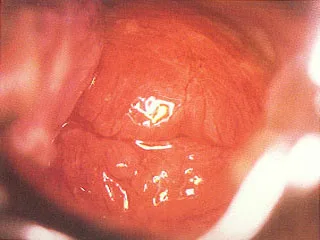

It is an electrical and optical high-tech diagnosis system merging computer technology, optics, imaging study, ergonomics principles and colposcopy, so that it can have more accurate evaluation on the border sector where we are not able to see by our naked eyes and bring more comprehensive solution to diagnosis and treatment of diseases.

1. Vaginal exfoliative cytology smear examination is more than three Pap levels.

2. Cytological examination is negative, but the naked eye observation has the suspicion of cancer

3. Long-term treatment in accordance with cervicitis, but the effects are not good.

4. The minor structural form of the lesions is difficult to determine by the observation with the naked eye.

5. The disease site and its spread part that can only be determined under the electric colposcopy before cervical cancer surgery